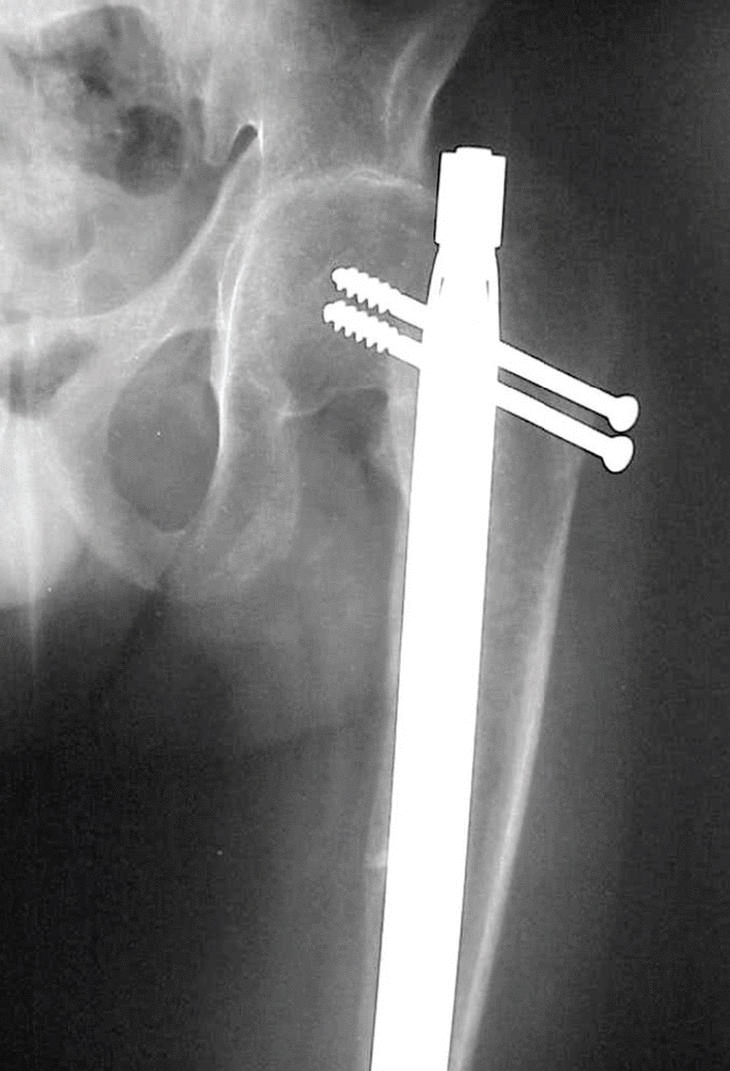

En enero de 2001 ingresa con una fractura del fémur izquierdo que se trata con un clavo no fresado y expansible (FIXION®); en el momento de la introducción se realiza una inserción muy medial y se le fractura la base del cuello femoral, lo cual se resuelve con 2 tornillos de esponjosa (figs.2 y 3). Evoluciona de manera satisfactoria y a las dieciséis semanas existe evidencia de consolidación (figs. 4A y B).

Fig. 2. Postoperatorio inmediato con clavo no fresado y expansible (FIXION ®), donde se evidencia lacolocación medial del clavo y la fractura basicervical.

Fig. 3. La fractura basicervical se resolvió con dos tornillos de esponjosa ( postoperatorio).